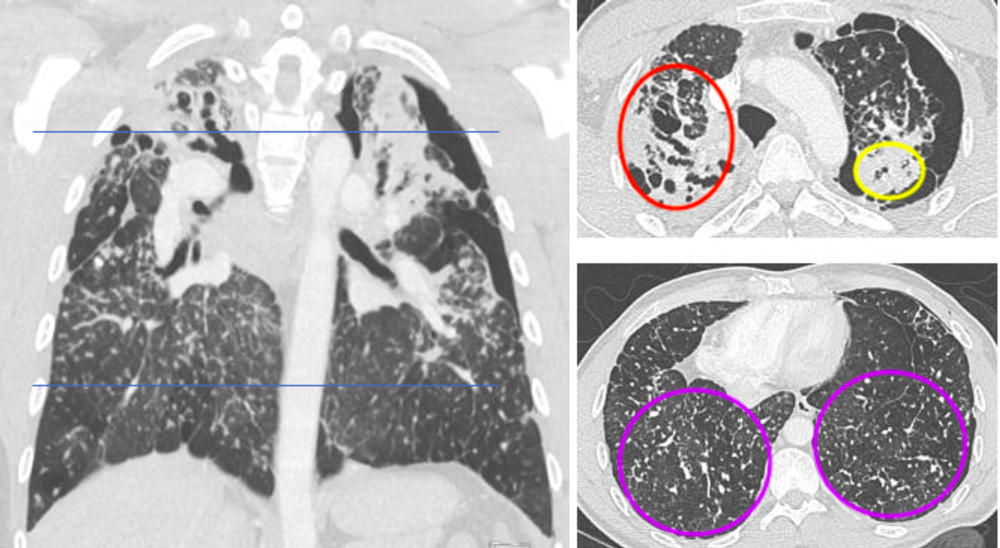

Figure 3. Contrast-enhanced chest computed tomography (CT) with upper predominant fibrosis/lung scarring (red oval), solid masses adjacent to a left-sided pneumothorax (yellow oval) and diffuse silicotic nodules (purple circle). This patient had a history of working in the countertop-cutting industry (15 years), smoking cigarettes (10 pack-years), and active tuberculosis (treated 7 years prior and excluded at the time of this image with laboratory testing).